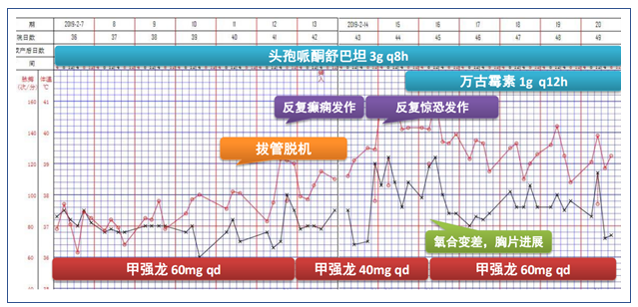

根据患者临床表现及检查结果,再次调整治疗方案(图10)。

根据患者情况又调整了治疗方案(图13)。患者2月11日拔管脱机,再次出现高热,谵妄反复发作,胡言乱语,对外周刺激敏感,伴气促、低氧(SpO2:75%~85%)。

此患者这一阶段肺内渗出病灶明显增多,可以从三方面考虑:①目前患者的原发病依然没有明确;②激素减量太快;③继发感染,如PCP,如果G试验阴性,则此种可能性偏小。

调整治疗方案后,患者各项生命体征逐步改善(图15)。